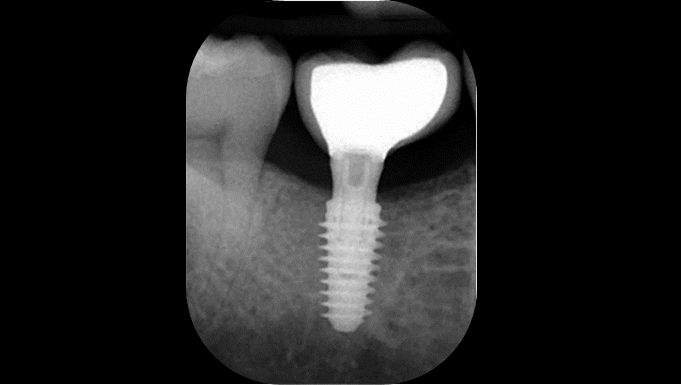

Clinical case: Installation of dental implants in complicated anatomic conditions using crest lifting methods

- Courtesy of Dr.Alexander Lysov, Russia -